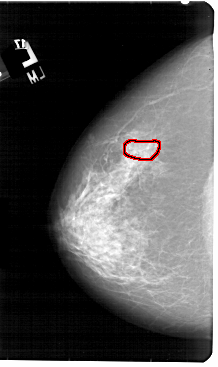

A_1954_1.LEFT_CC

LEFT_CC LINES 5491 PIXELS_PER_LINE 3256 BITS_PER_PIXEL 12 RESOLUTION 43.5 OVERLAY

FILE: A_1954_1.LEFT_CC.OVERLAY

TOTAL_ABNORMALITIES 1

ABNORMALITY 1

LESION_TYPE CALCIFICATION TYPE PUNCTATE DISTRIBUTION CLUSTERED

ASSESSMENT 4

SUBTLETY 3

PATHOLOGY BENIGN

TOTAL_OUTLINES 1

BOUNDARY